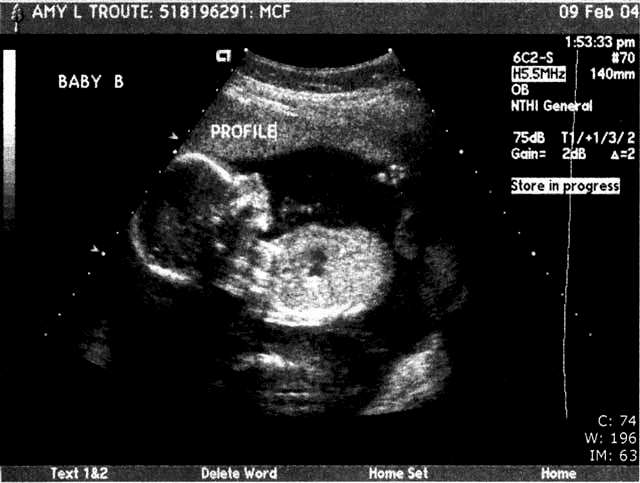

| We had our BIG ultrasound on February 9. Here are a few of the 111 pictures that were taken (everything from areas of the brain to little tiny kidneys) in our nearly 2-hour appointment (click the pictures to get a larger view – note the one where Baby A’s foot is right above Baby B’s head – so cute!!). The babies were moving so much that the tech had to literally hold them down with the ultrasound wand to get the detailed pictures she needed! Talk about uncomfortable!! Whew!! We were thrilled to hear that they’re developing perfectly – measuring in at 14cm and 9oz each!! They even bumped my due date up a week since the babies were measuring bigger than normal – music to our ears!! We’re still shooting for late June… I’d be at 36 weeks on my birthday – I’d love to share June 17 with the twins…or our anniversary June 23, or Father’s Day… ;o) We heard the heartbeats at a doctor’s appointment on 2/18 and my “theory” of their different heart rates signaling “boy and girl” was blown… In each of our past appointments there was a 10-15 beat difference between the two, but this time both were right at 160 beats per minute. I guess Reese is right – I really have no idea who’s in there! This week (2-16 to 2-20) I’ve started to really feel the babies moving! They’re especially active from 2-5 in the afternoon… makes it so hard to concentrate! I love it! I can't imagine how it's going to feel once they weigh more than 9 or 10oz each... Two 4 or 5lb kiddos in there packing on the pounds, rolling around and sticking their feet in each other's faces... Hahaha! What an image!! And the thought of them being most active at night... The adventure is only beginning!" |